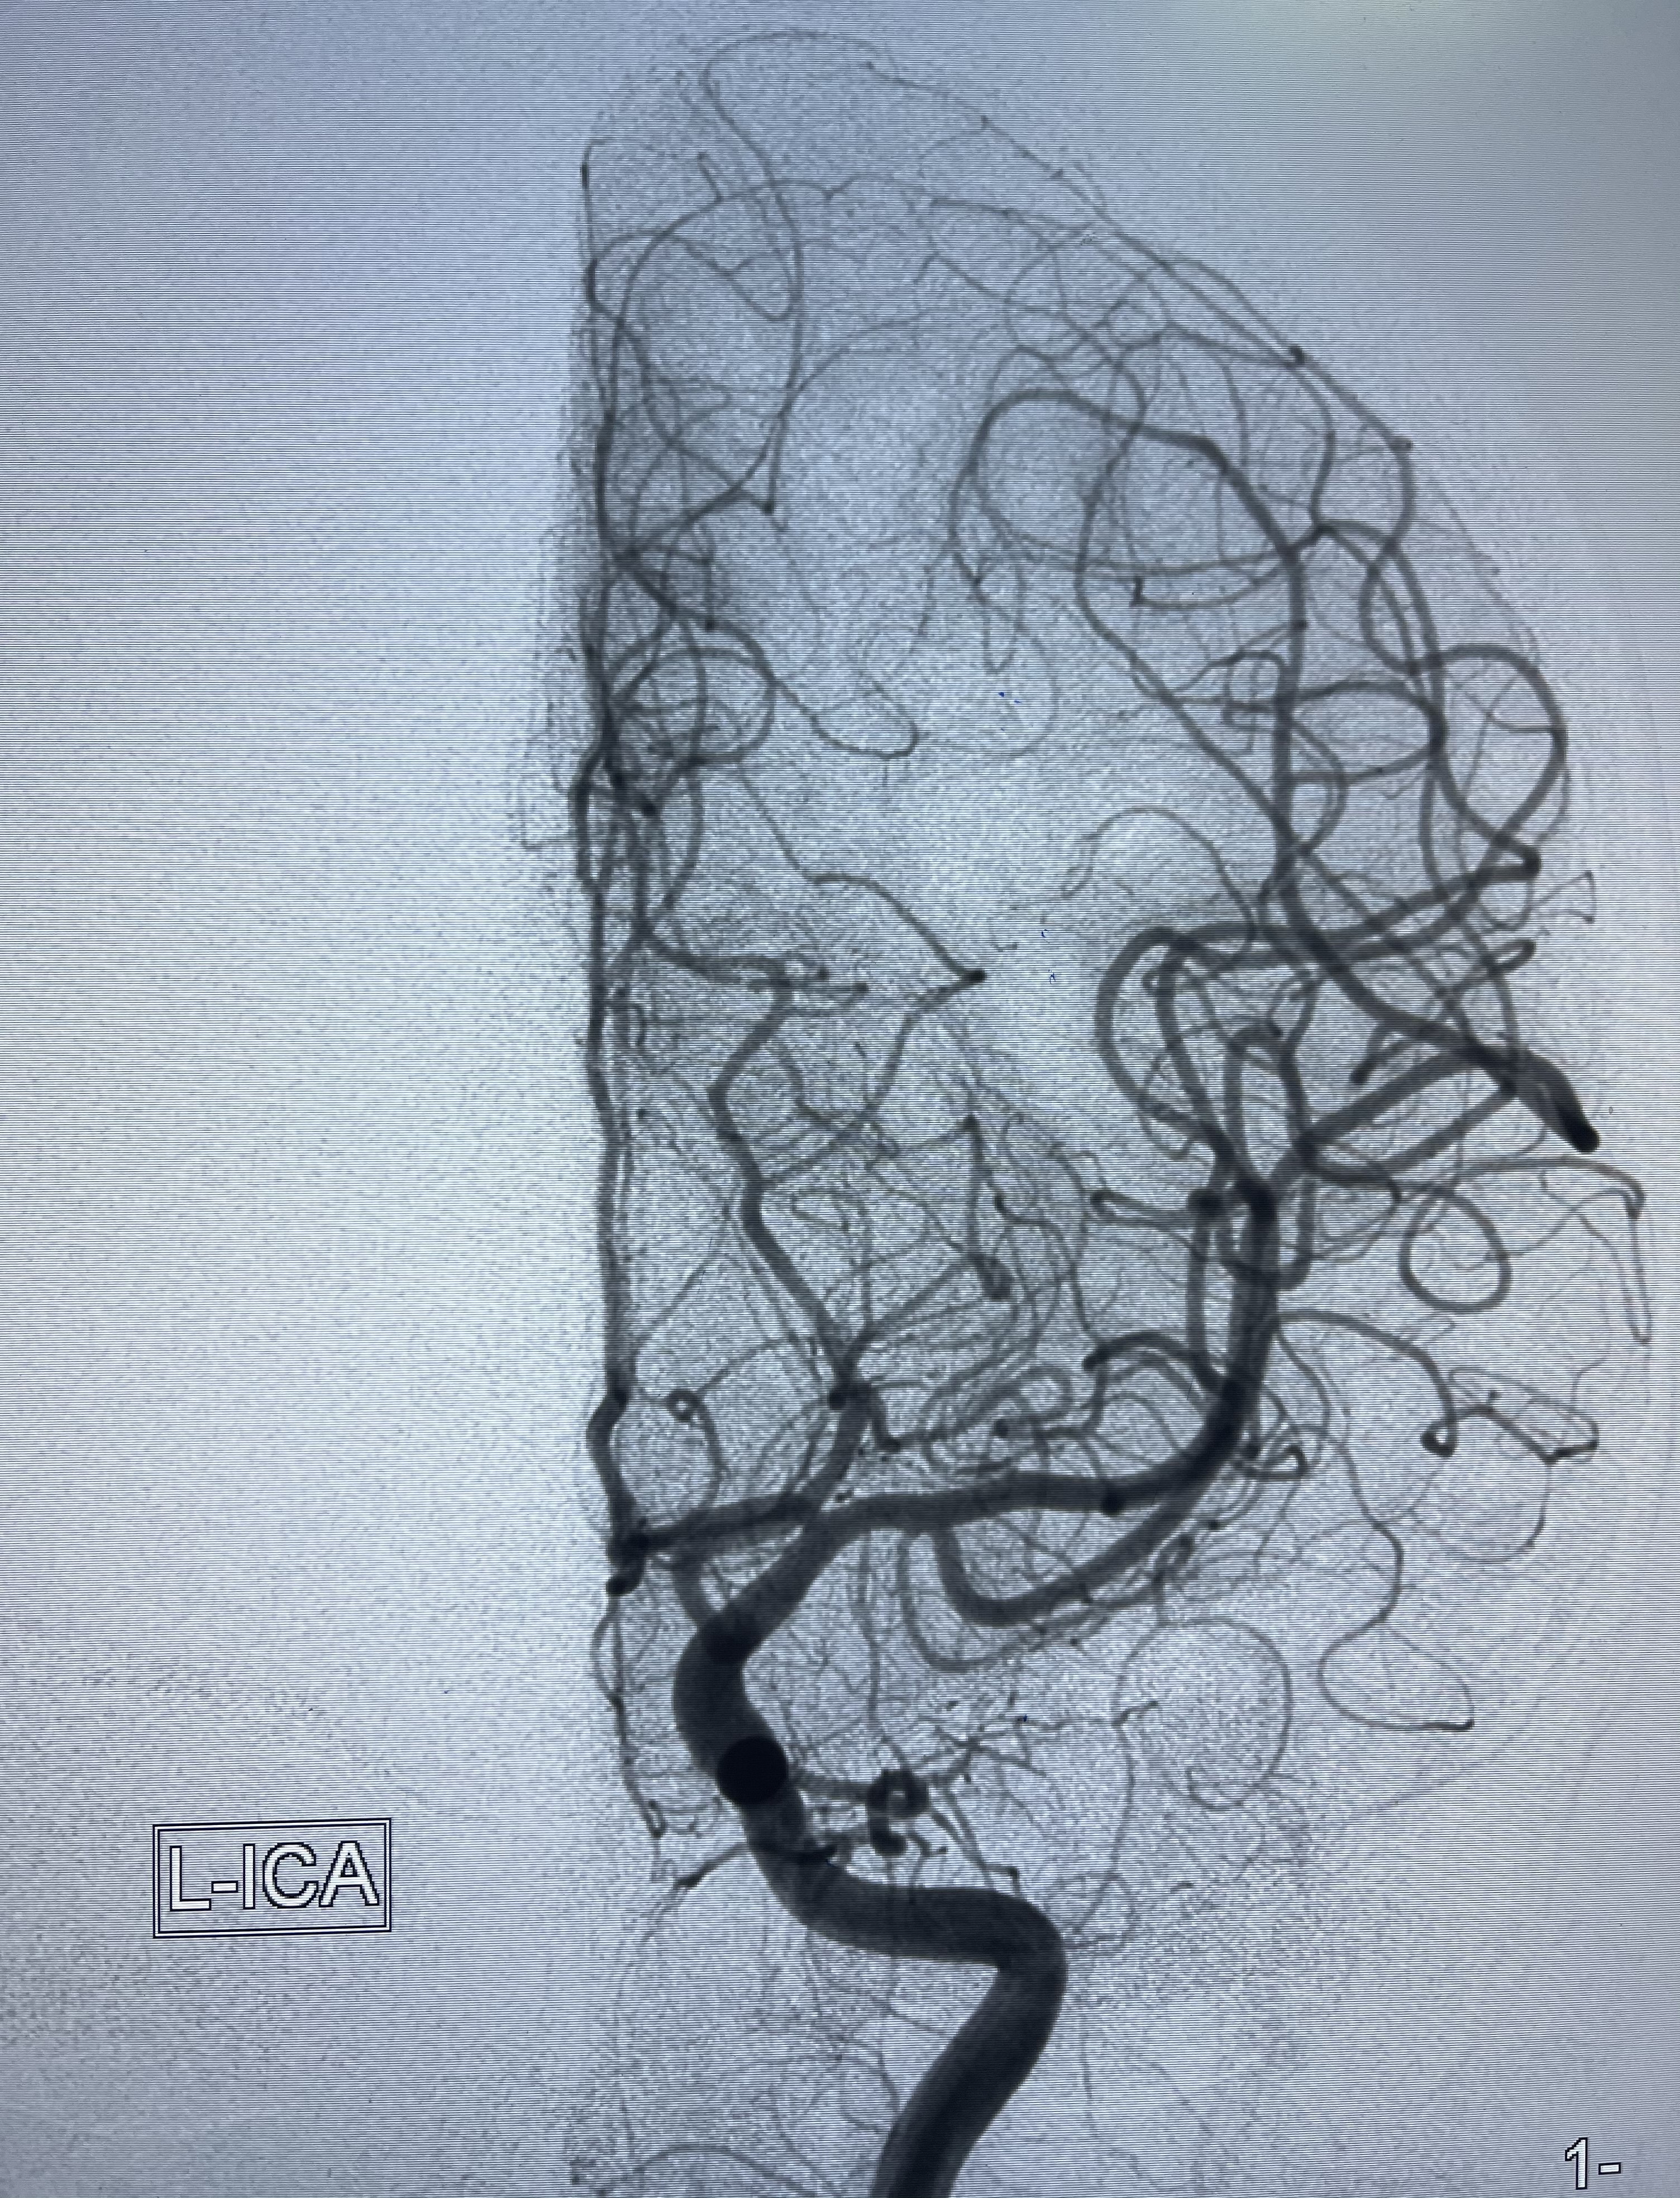

患者,女,33岁,因“头颈部疼痛伴恶心呕吐11周余”入院,有高血压病史六年余,最高时230/120mmhg。2020.10.09激动后出现头颈部疼痛,伴恶心呕吐,呕吐物为胃内容物,否认肢体乏力,否认两便失禁,否认意识不清,2020.10.12平湖市第一人民医院查头颅CT提示“左侧基底节区点状出血,脑室系统少量积血,蛛网膜下腔出血”,查头颅CTA提示“前交通动脉瘤”,经予以积极对症治疗,恢复尚可,头痛基本缓解。目前恢复尚可,现为进一步诊治收入病房。

2021-01-07DSA

右侧前交通动脉瘤

箭头所示为左侧A2发出